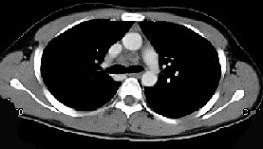

问题 男,21岁,干咳,盗汗一月伴消瘦,CT如图,应先考虑为 ( )

选项 A、右上肺上沟瘤 B、右上肺不张 C、纵隔型肺癌并纵隔淋巴结核转移 D、淋巴瘤 E、右上肺结核并纵隔淋巴结核

答案 E